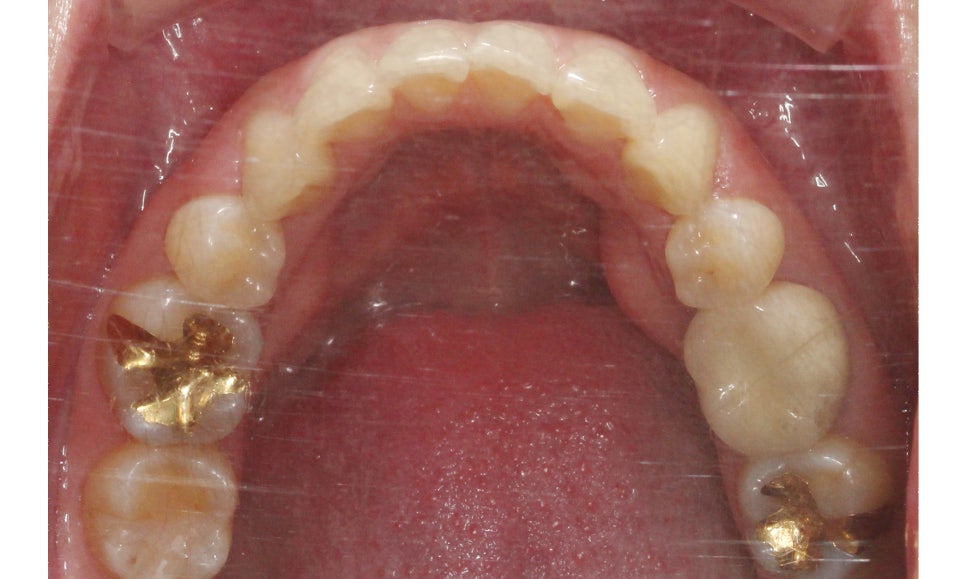

대치동치과 교정 전 하악의 치아배열은

위처럼 전치부가 삐뚤삐뚤하게

배열된 모습인데요, 상악에 비해

비교적 심하지 않은 Crowding으로

보이는 모습입니다.